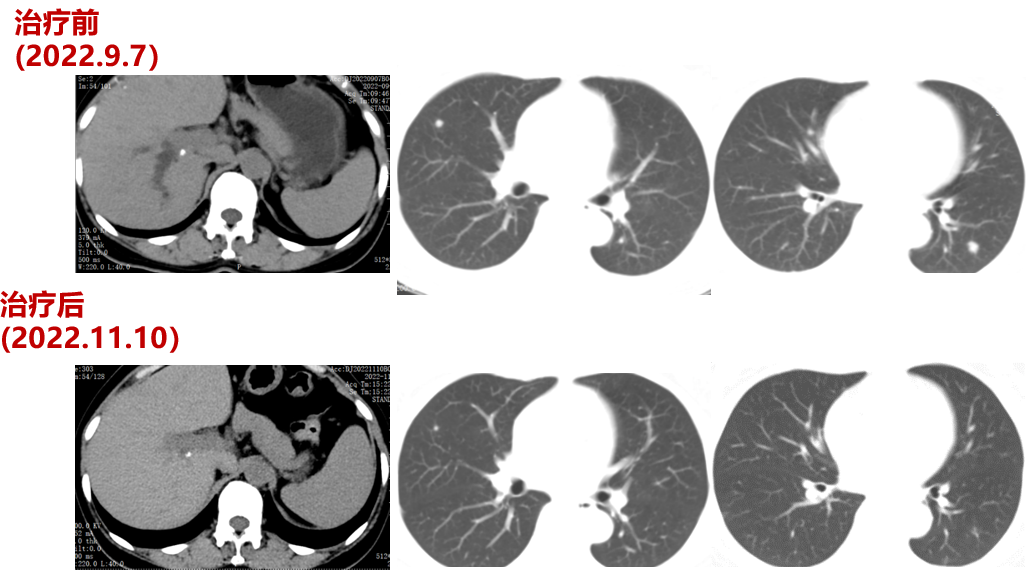

三线治疗(2022-9-7至2023-03-18,PFS:6月余):

2022-09-07至2023-01-03院外使用DS-8201治疗5周期。2周期后疗效评价:PR。CT示:腹膜后淋巴结较前部分缩小;双肺多发转移灶较前缩小。